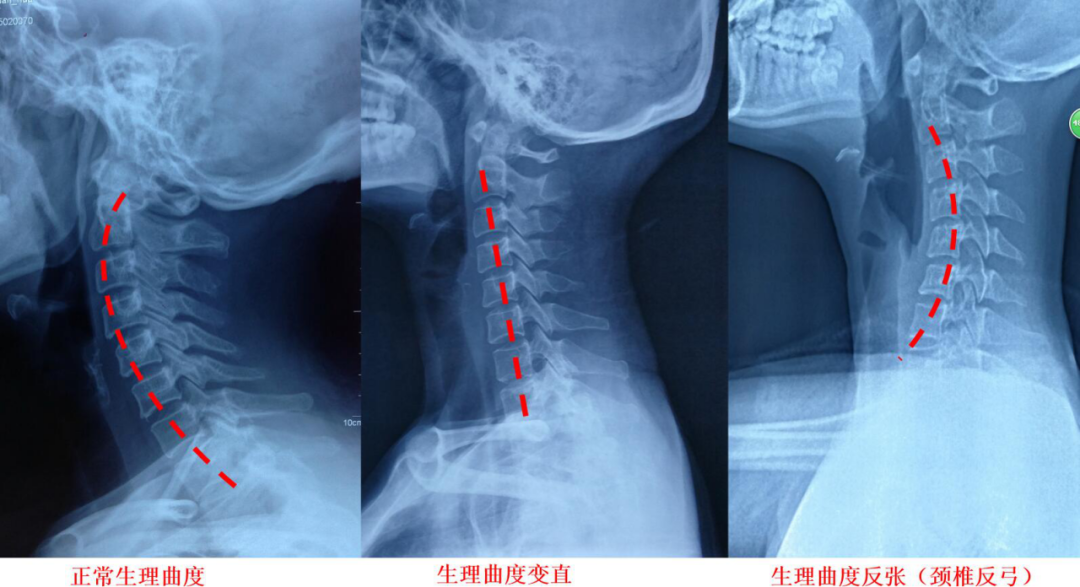

手外科主任邱庆明经过仔细地问询和检查,发现他普遍是在低头过久后才产生头晕现象,并伴有双手麻木、双腿乏力等症状,最后确诊为颈椎曲度反弓。